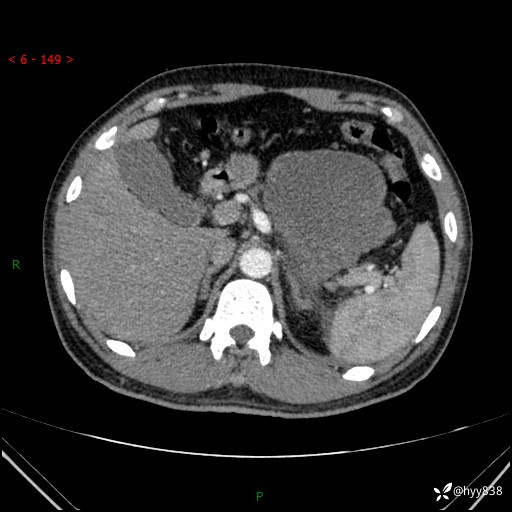

病例39岁/女,左侧腰痛入院。腹腔囊实性肿块,定位、定性---结果公布~

性别:男

年龄:39岁

简要病史:左侧腰痛待查,CT发现腹腔占位

腹部CT平扫+增强